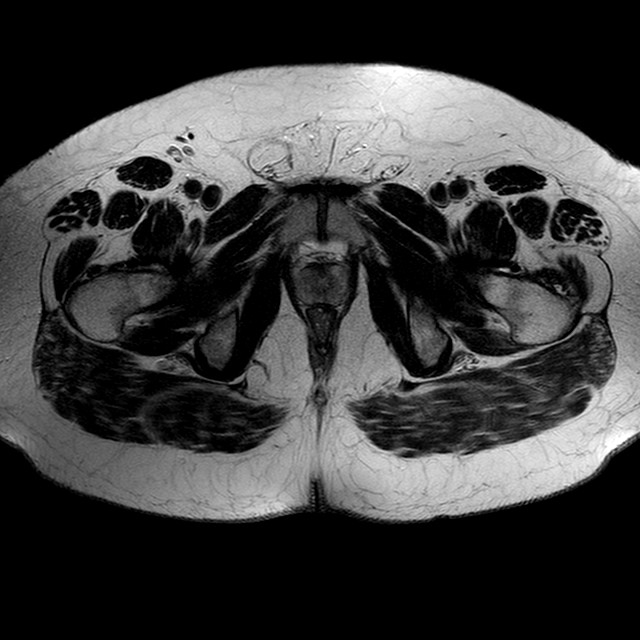

Esami: RMN BACINO

T2w TSE

Evidenti e simmetriche alterazioni osteofitosiche in regione coxo femorale con riduzione delle rime articolari. Degenerazione completa del cercine glenoideo. Non attuali segni di versamento articolare. Non segni di edema osseo che escludono attuale algodistrofia od osteonecrosi. Lieve e simmetrica riduzione del trofismo della muscolatura glutea.